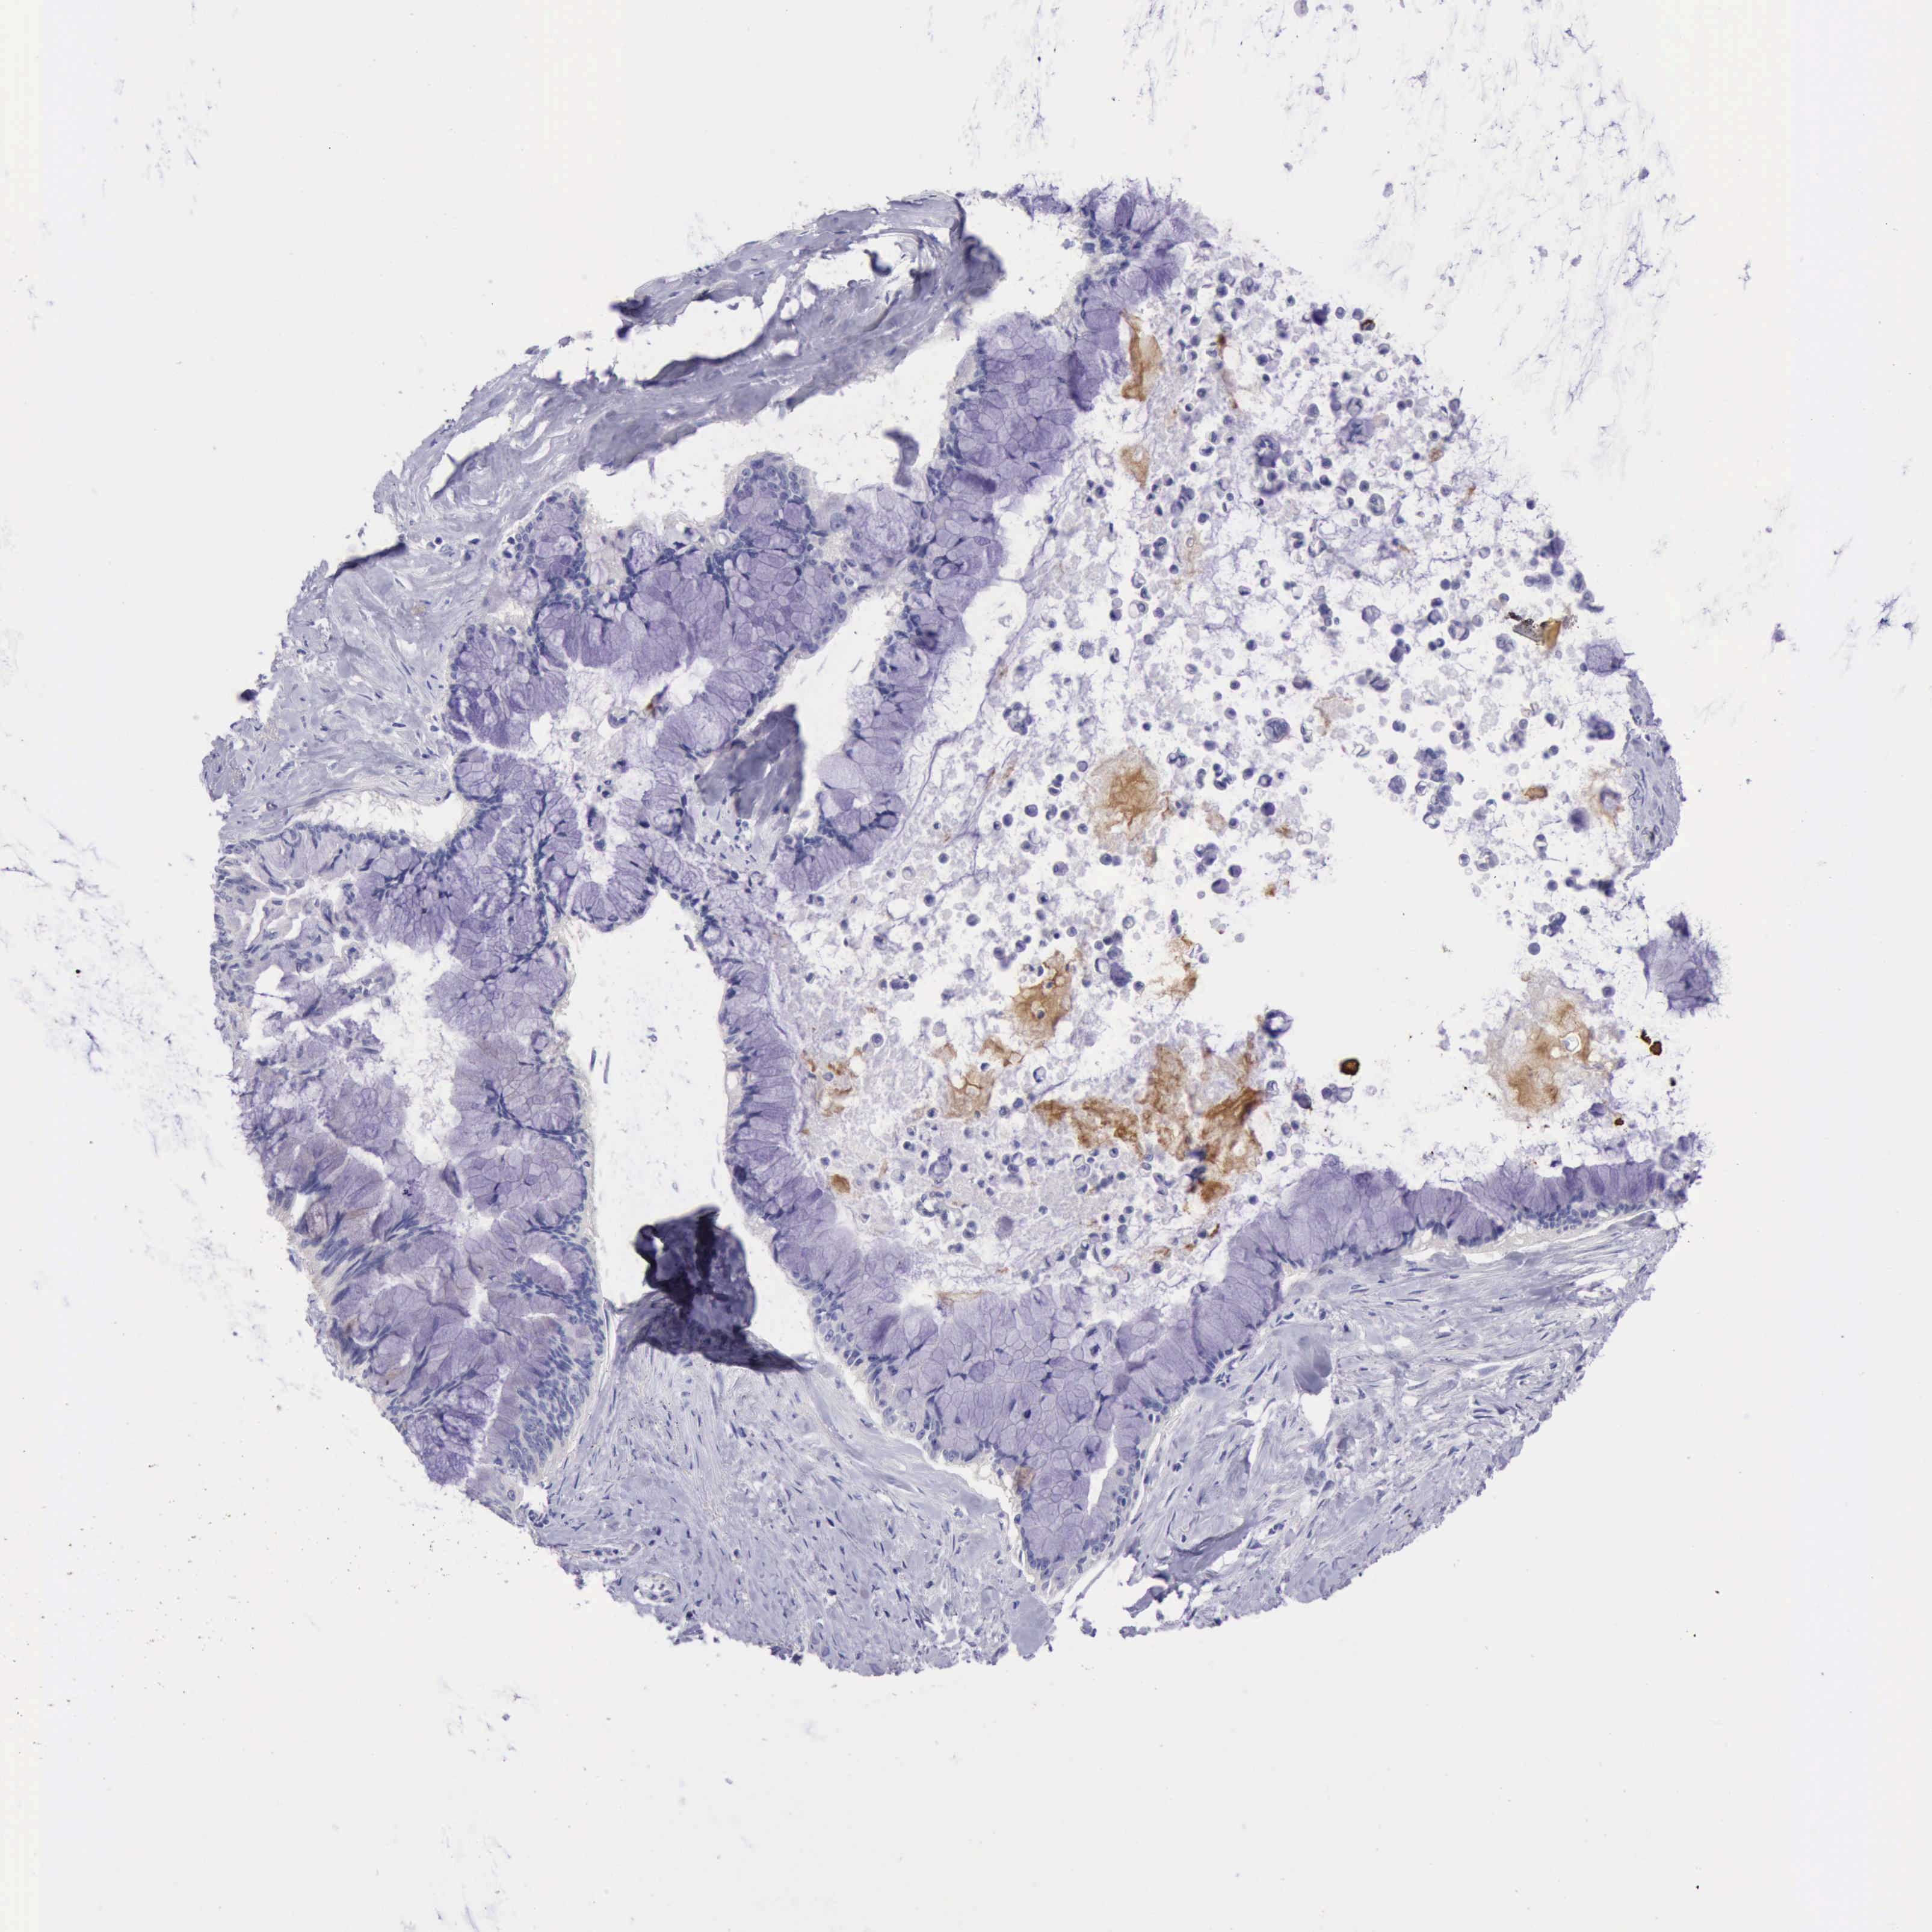

PANCREATIC CANCER - Protein expressioni

A mouse-over function shows sample information and annotation data. Click on an image to view it in a full screen mode. Samples can be filtered based on level of antibody staining by selecting one or several of the following categories: high, medium, low and not detected. The assay and annotation is described here.

Note that samples used for immunohistochemistry by the Human Protein Atlas do not correspond to samples in the TCGA dataset.

Antibody stainingi

Antibody staining in the annotated cell types in the current human tissue is reported as not detected, low, medium, or high, based on conventional immunohistochemistry profiling in selected tissues. This score is based on the combination of the staining intensity and fraction of stained cells.

Each image is clickable and will lead to virtual microscopy that enables deeper exploration of all samples and also displays staining intensity scores, fraction scores and subcellular localization as well as patient and tissue information for each sample.

Antibody HPA001177

Staining

High

Medium

Low

Not detected

Intensity

Strong

Moderate

Weak

Negative

Quantity

>75%

75%-25%

<25%

None

Location

Nuclear

Cytoplasmic/membranous

Cytoplasmic/membranous,nuclear

Adenocarcinoma, NOS